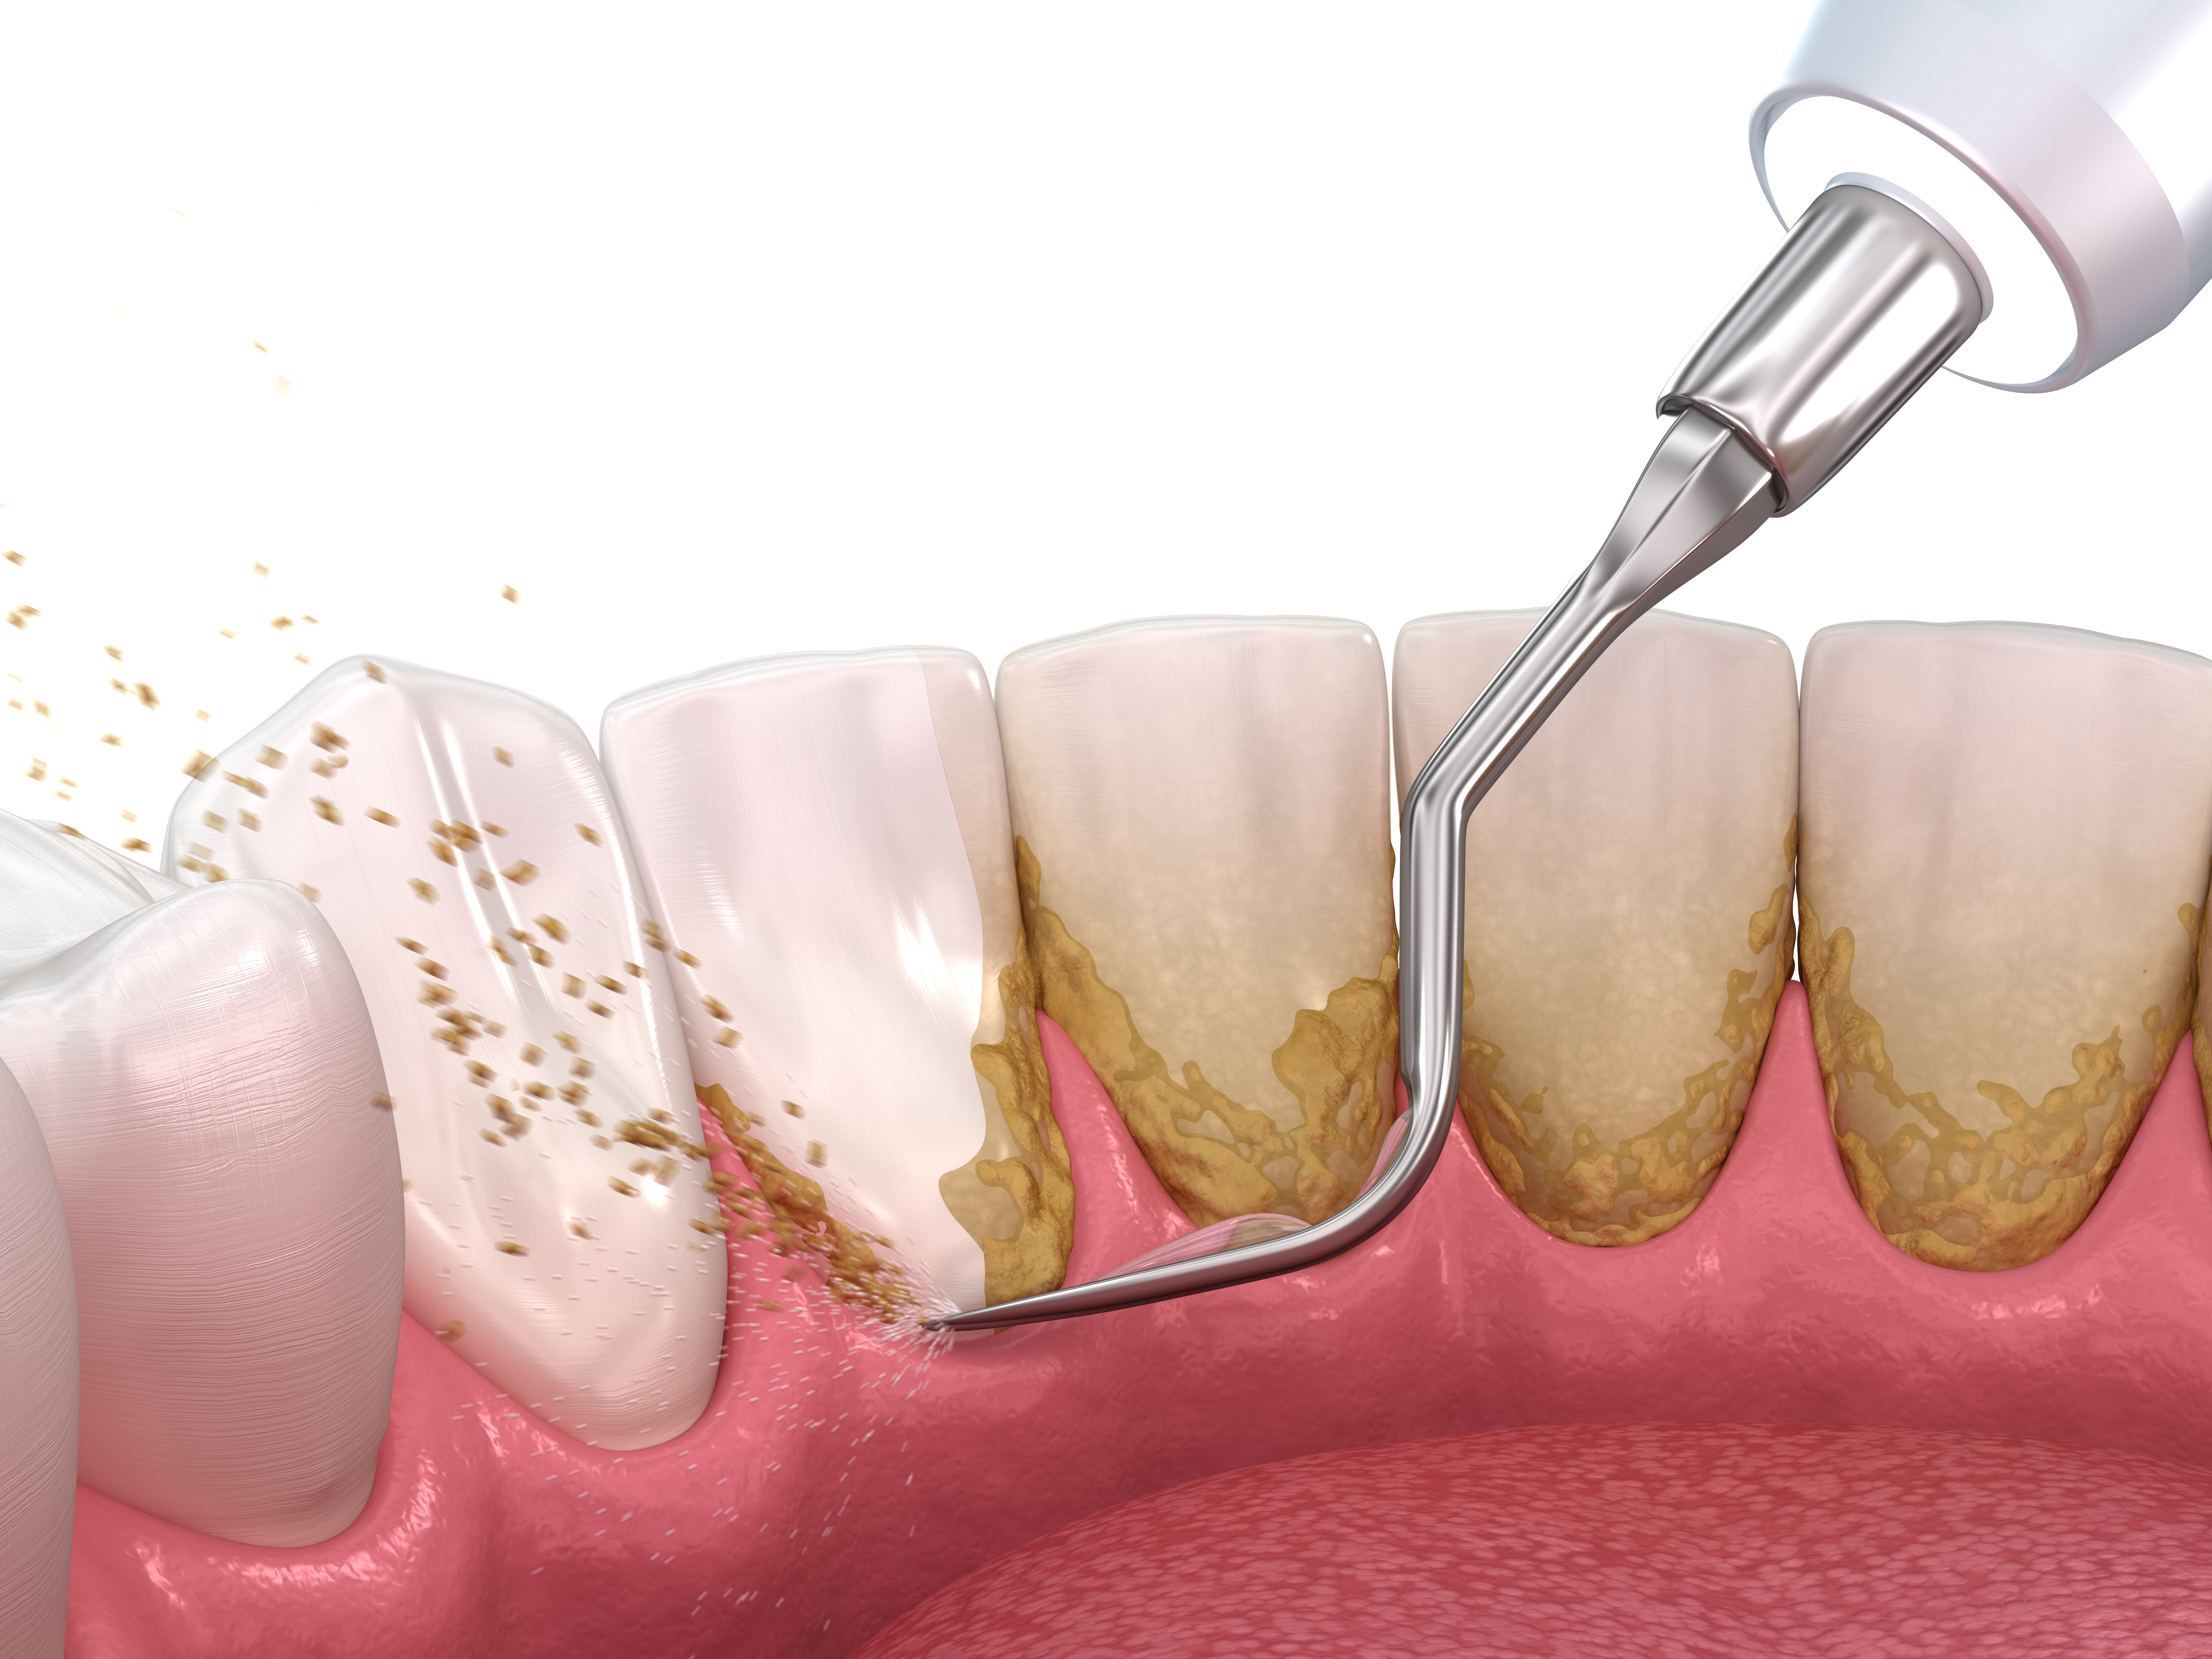

基本治療(初期治療)

歯周病の原因となる歯垢や歯石を徹底的に除去します。専門的なクリーニングやスケーリング、ルートプレーニングと呼ばれる処置を行い、歯周ポケットの奥深くまできれいにします。また、ご自宅での正しい歯磨き方法についても丁寧に指導します。